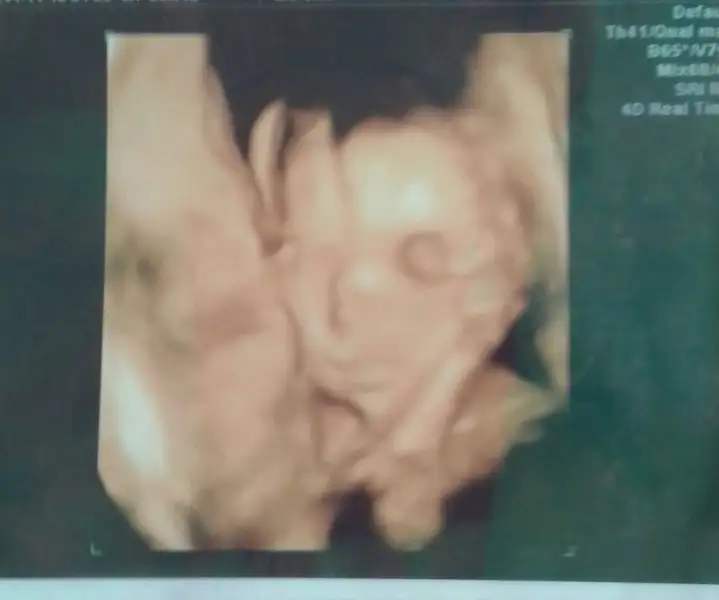

Ayy ya nasil guzel nasil net heycanlandm.smdiEki Görüntüle 1997484 Eki Görüntüle 1997484 Eki Görüntüle 1997485 kizlar 22 haftalikken yapmıştım 5aylik bebeğin renkli usg görüntüsü

maşallahEki Görüntüle 1997484 Eki Görüntüle 1997484 Eki Görüntüle 1997485 kizlar 22 haftalikken yapmıştım 5aylik bebeğin renkli usg görüntüsü